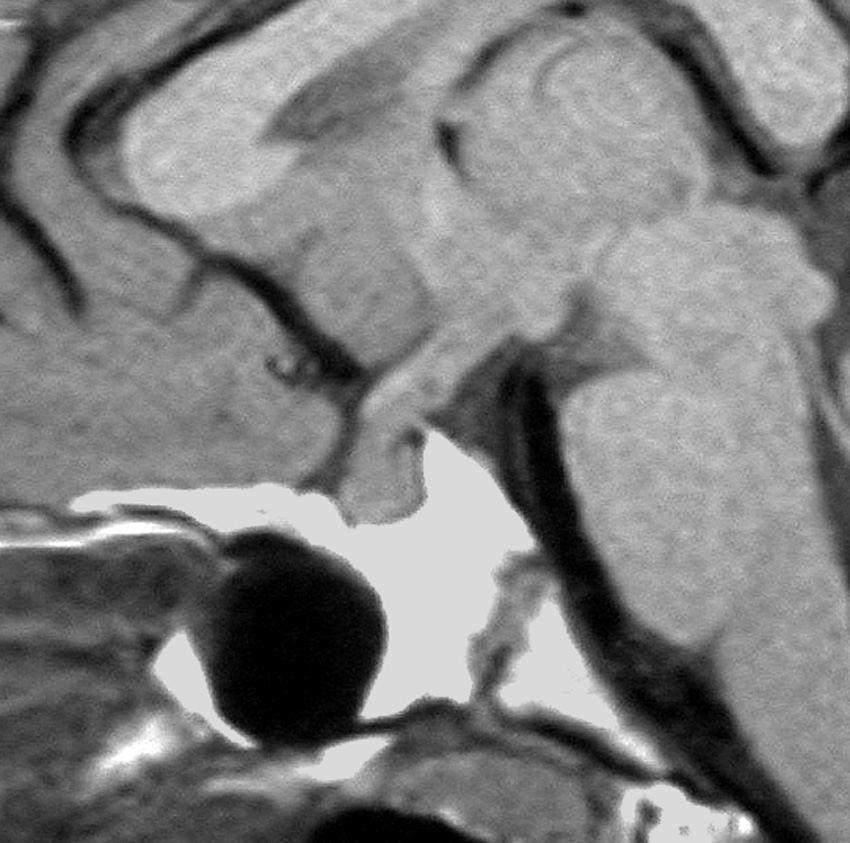

この例は古いので第3脳室開窓術 ETV をしていません。左はICE化学療法前。中央は9日後。右は25日後です。閉塞性水頭症があっても1週間くらいで中脳水道が通って水頭症は改善します。ジャーミノーマであれば,ICE化学療法1コースでかなり縮小するはずです。このような顕著な効果がない時には,逆にジャーミノーマ以外の胚細胞腫瘍が混在していると考えた方がいいでしょう。多くは奇形腫の混在です。